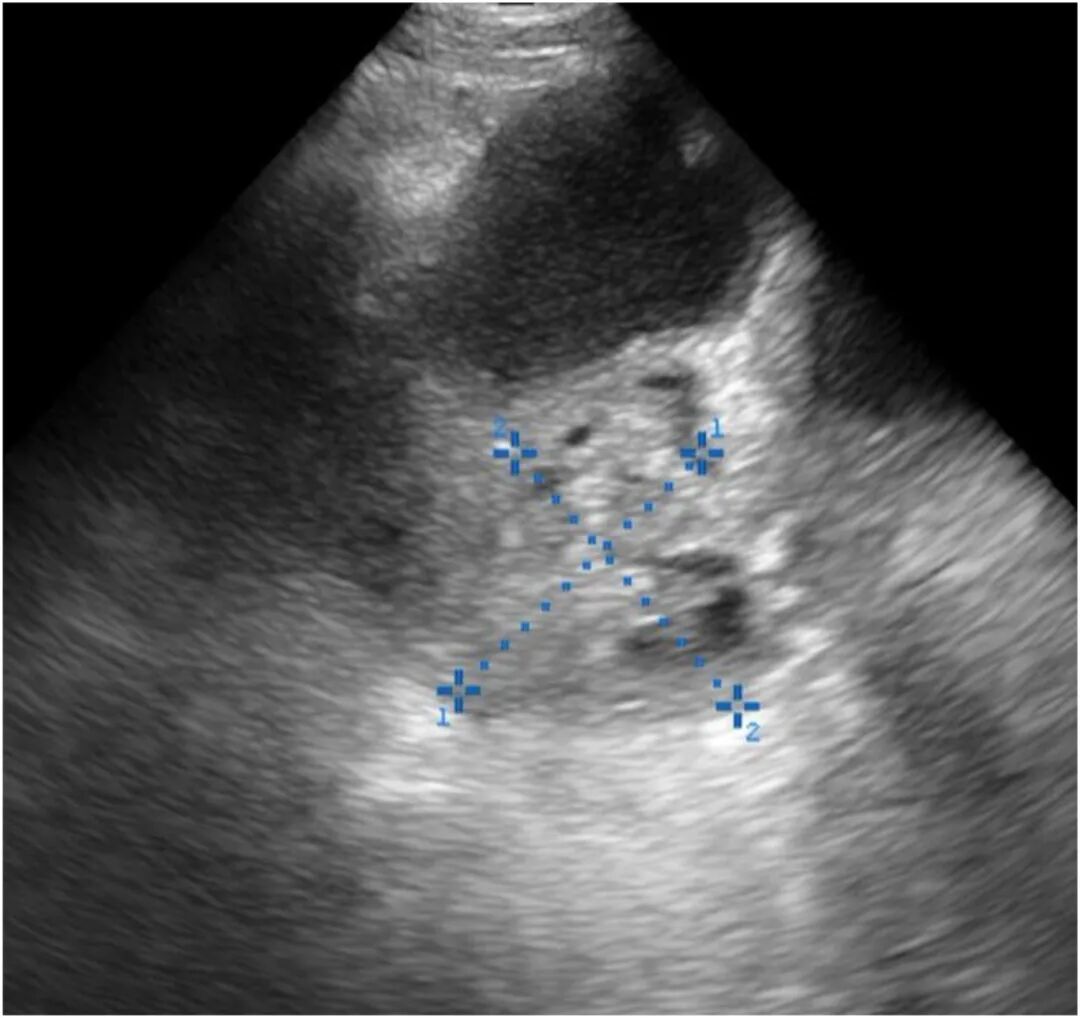

图2 床旁即时超声经腹部左侧盆腔矢状面成像显示:一复杂性炎症性卵巢(游标测量4.0×4.0 cm),毗邻上述液性聚集区。

入院后,查体示体温37.9℃,左下腹压痛伴反跳痛。实验室检查显示白细胞计数13.1×10⁹/L,C反应蛋白水平10 mg/dL(100 mg/L),妊娠试验阴性。行床旁超声检查,显示左下腹存在一大型管状结构,内见单纯性回声,并见复杂性炎症性卵巢(图1、图2)。